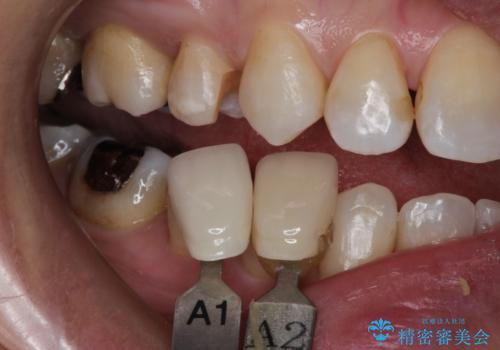

笑ったら銀歯が見える。 セラミックインレーによる治療

- 笑ったときに銀の詰め物が見えることを主訴に来院されました。

セラミックインレーにて修復を行いました。

- 7万円費用は治療当時の料金となります

保険治療で使える材料には制限があり、見た目だけでなく精度でも劣ります。当院でのセラミックインレーは歯とのつなぎ目を拡大鏡で確認して精度高く仕上げるため、むし歯のリスクを限りなく少なくできるよう治療します。